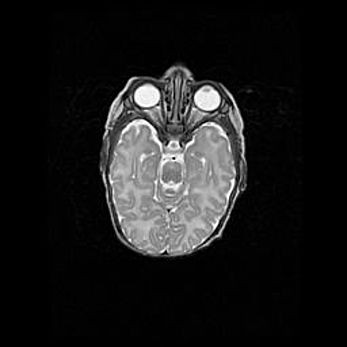

Множественные кисты обоих полушарий головного мозга, наибольшая из них в правой затылочной области. Ассиметричная атрофическая гидроцефалия.

Возраст: 7 месяцев

Вес: 5660 г

Пол: мужской

Окружность головы: 41,5 см

Срок гестации: 28-29 недель

Кисты головного мозга развиваются в результате многоочаговых некрозов вещества мозга и возникают вследствие перенесенной перинатальной инфекции, менингитов, энцефалитов, асфиксии, родовой травмы, расстройств мозгового кровообращения различного генеза. Образованию кист в веществе головного мозга плодов и новорожденных способствуют такие факторы, как высокое содержание в нем воды, недостаточная (или отсутствие) миелинизация и слабая астроглиальная реакция на повреждение.

Кисты могут сочетаться с гидроцефалией и другими поражениями головного мозга.